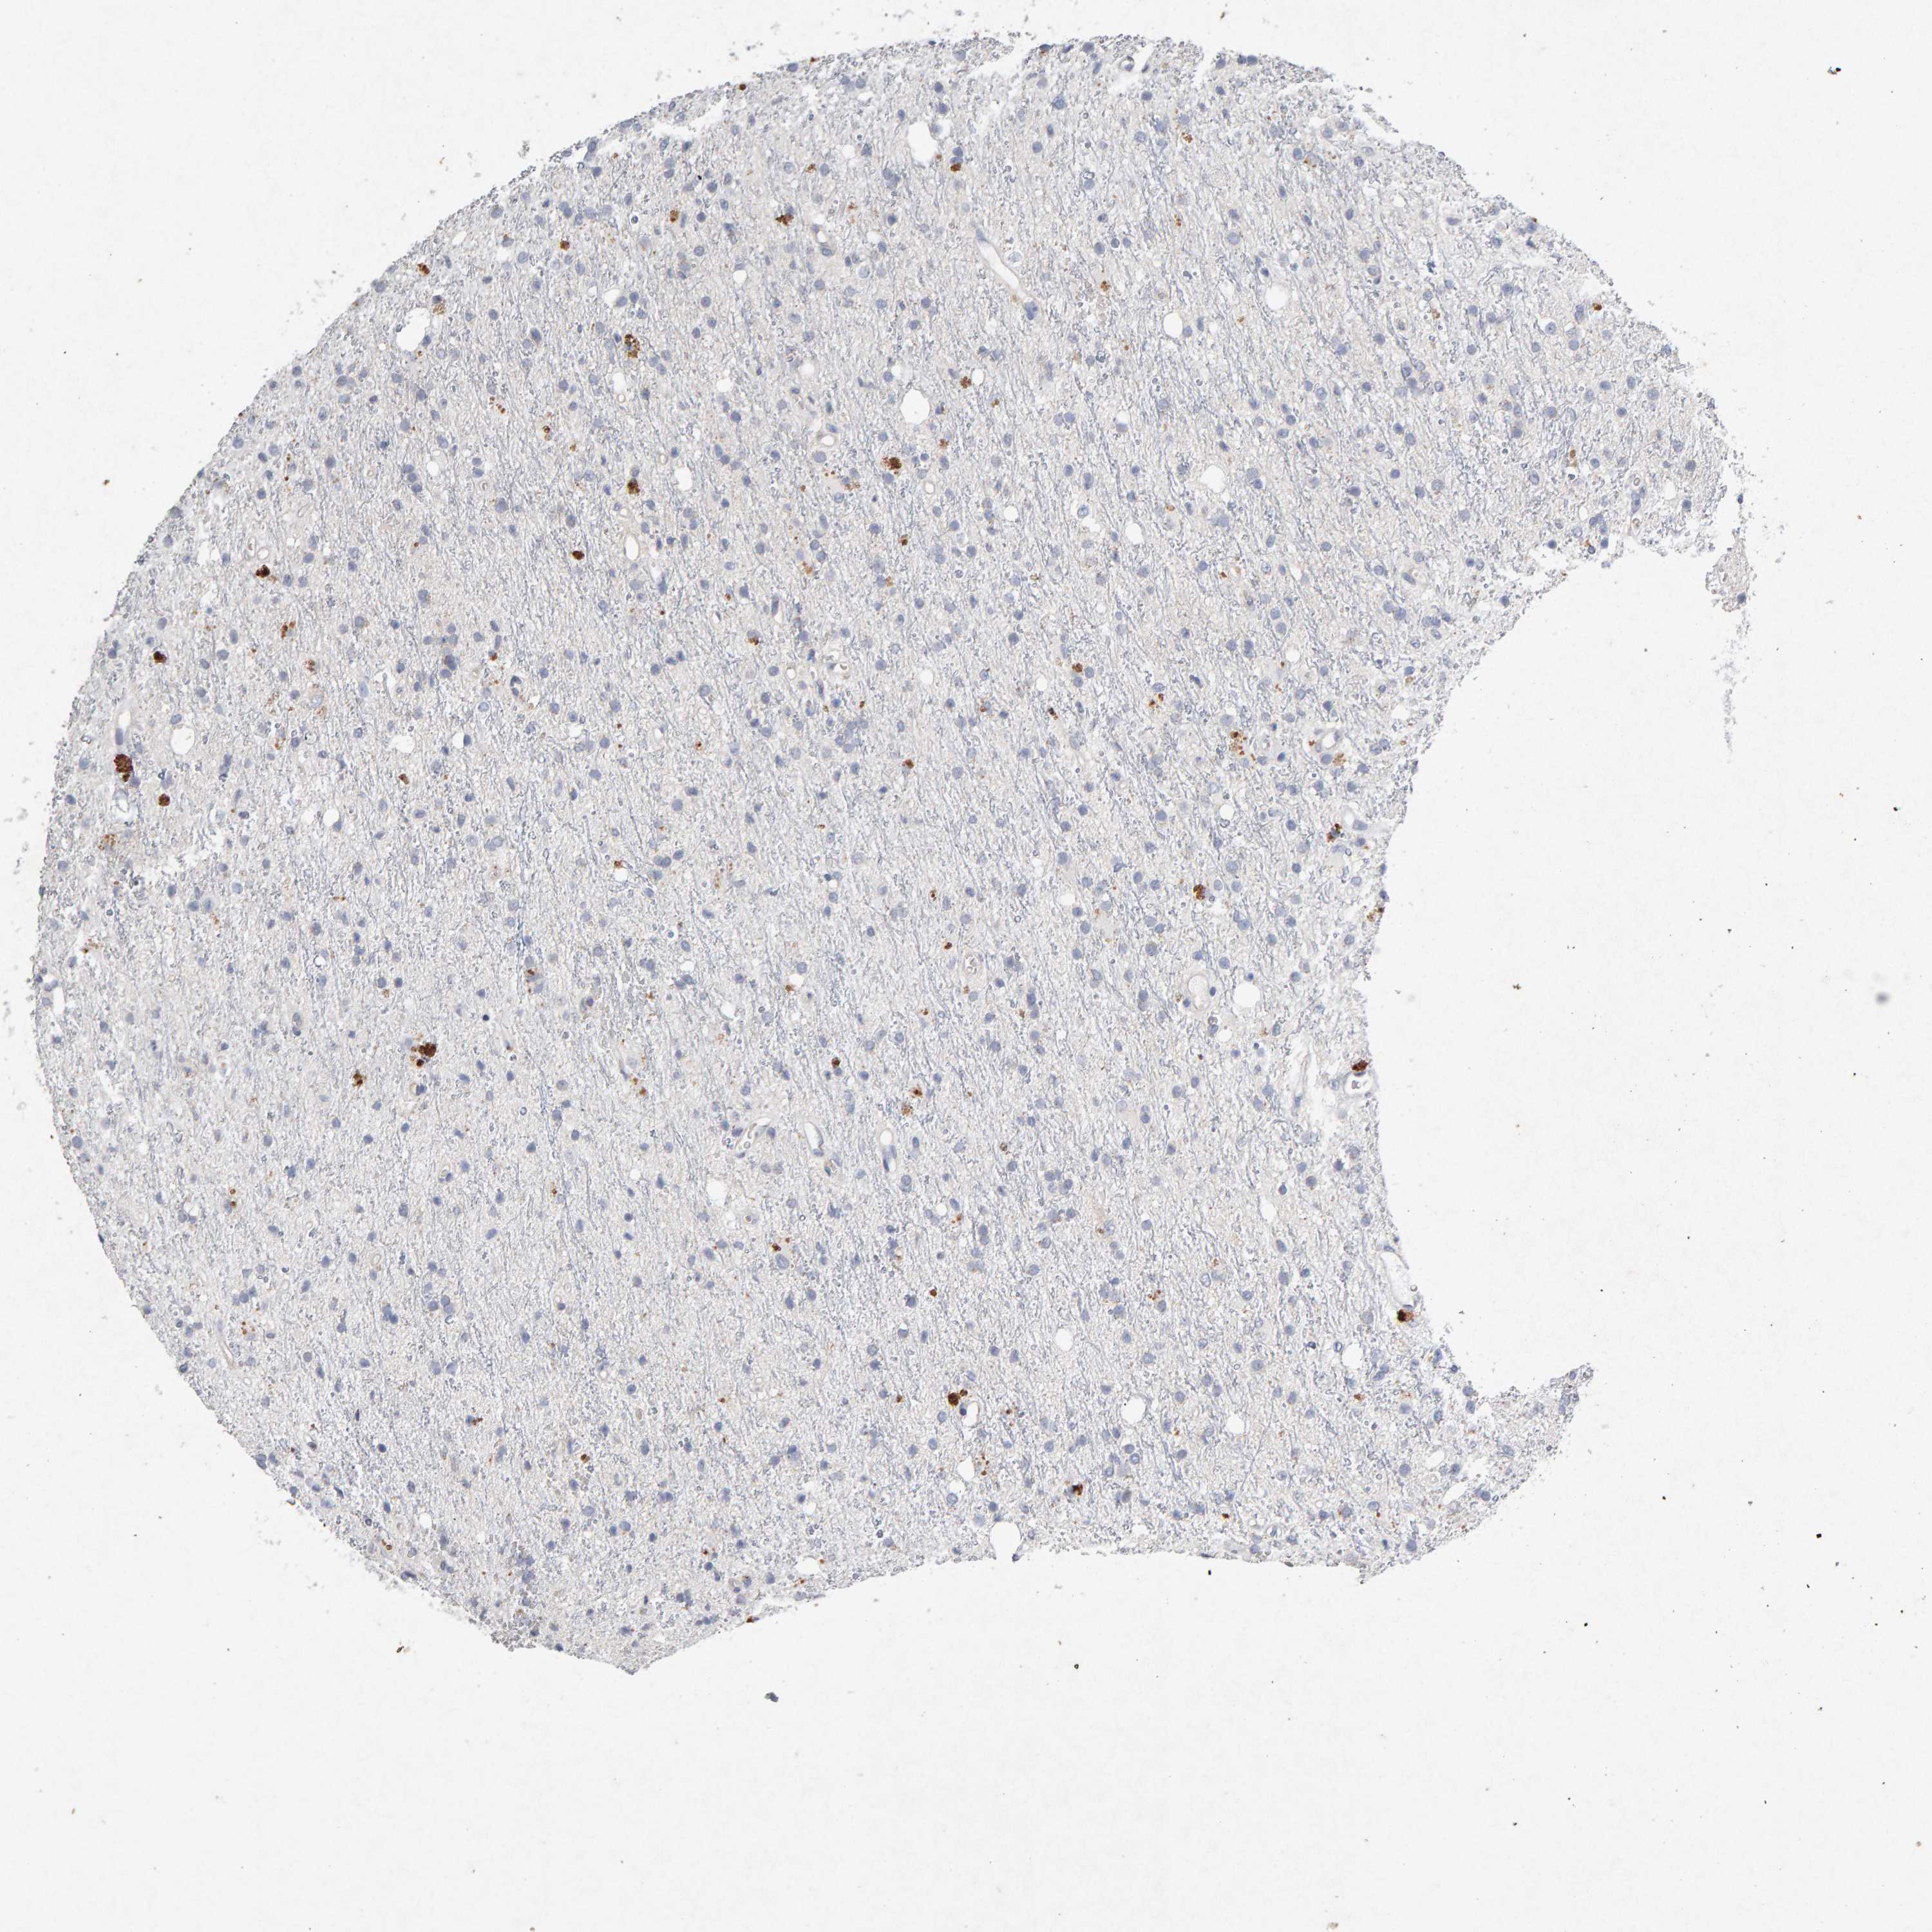

GLIOMA - Protein expressioni

A mouse-over function shows sample information and annotation data. Click on an image to view it in a full screen mode. Samples can be filtered based on level of antibody staining by selecting one or several of the following categories: high, medium, low and not detected. The assay and annotation is described here.

Note that samples used for immunohistochemistry by the Human Protein Atlas do not correspond to samples in the TCGA dataset.

Antibody stainingi

Antibody staining in the annotated cell types in the current human tissue is reported as not detected, low, medium, or high, based on conventional immunohistochemistry profiling in selected tissues. This score is based on the combination of the staining intensity and fraction of stained cells.

Each image is clickable and will lead to virtual microscopy that enables deeper exploration of all samples and also displays staining intensity scores, fraction scores and subcellular localization as well as patient and tissue information for each sample.

Antibody CAB022442

Antibody CAB022443

Staining

High

Medium

Low

Not detected

Intensity

Strong

Moderate

Weak

Negative

Quantity

>75%

75%-25%

<25%

None

Location

Nuclear

Cytoplasmic/membranous

Cytoplasmic/membranous,nuclear

Glioma, malignant, High grade

Glioma, malignant, Low grade